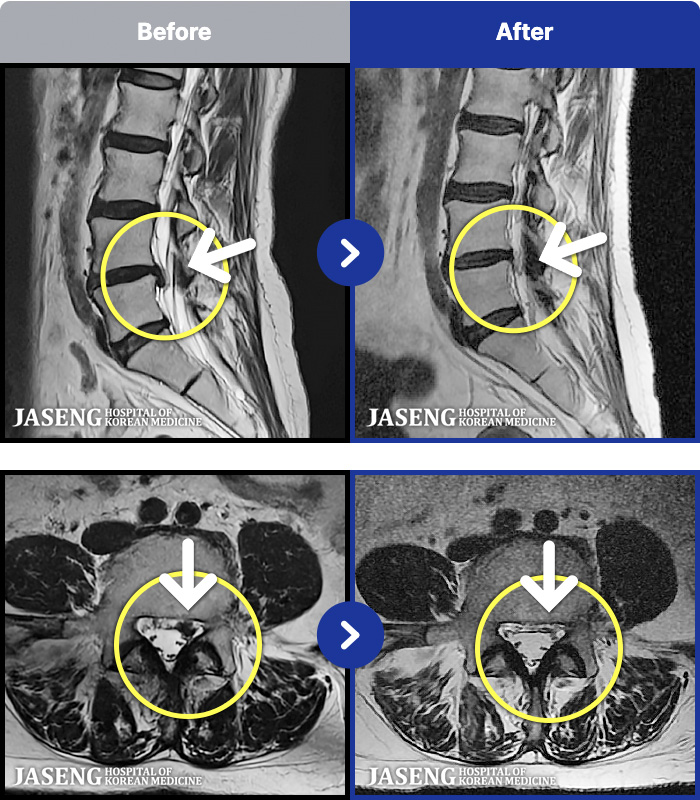

[뱸] 19.11.28~25.05.06